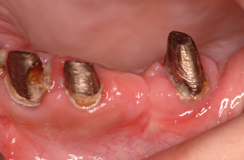

インプラントは歯茎の中の骨がないと植立できません。そのため、その骨が足りない場合が一番、インプラントをする上で問題となります。下顎では過下顎神経管という太い神経が顎の骨の中に通っていますので歯茎からその神経が近い場合骨移植が必要となります。また、上顎では太い神経はありませんが、副鼻腔という大きな空洞が顎の中にありますので、歯茎から副鼻腔が近い場合も骨移植が必要となります。

骨移植はインプラント埋入より、高度な技術が必要ですのでなるべくこの処置をしなくて済むように考案されたのがオールオン4などのコンセプトです。しかし、オールオン4ができないくらい骨がたりない場合などには行います。